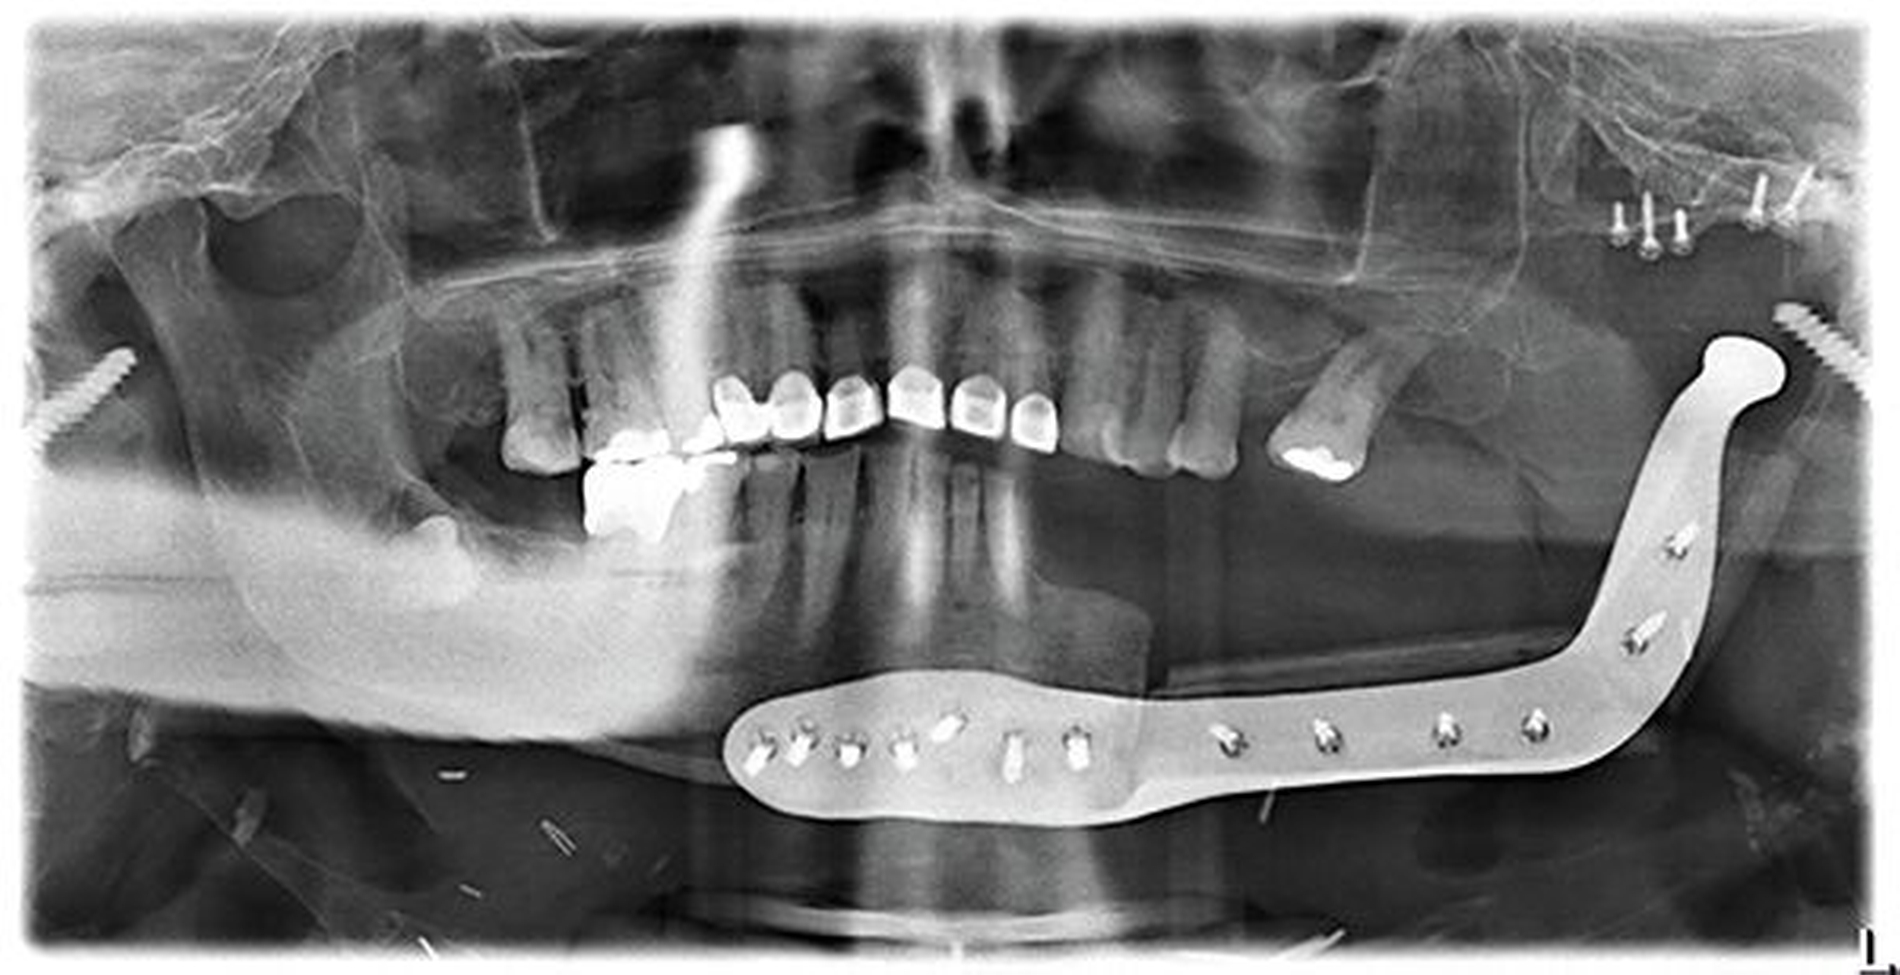

In der Kontrolle mittels Orthopantomogramm (OPG) zeigte sich dann die Fraktur der Rekonstruktionsplatte (Abbildung 1). Das proximale Fragment mit Kondylus war in seiner Dimension zu gering, um eine erneute belastungsstabile Osteosynthese durchführen zu können. Als Option stand hier die TEP zur Verfügung. Für die ossäre Mandibularekonstruktion entschieden wir uns, gleichzeitig ein zweiteiliges Fibulatransplantat als composite graft zu transplantieren.

Das postoperative OPG (Abbildung 10) zeigt die Übereinstimmung von Planung und Realität. Die Fossakomponente ist in der röntgenologischen Bildgebung nicht sichtbar, da das verwendete Material aufgrund der Biokompatibilität und Abriebsfestigkeit nicht röntgenopak ist.

Abbildung 14 zeigt das postoperative OPG. Durch die optimale Planung konnte die Kollision von Implantaten, PSI und Fixationsschrauben vermieden werden, was somit die Implantation erst möglich machte.